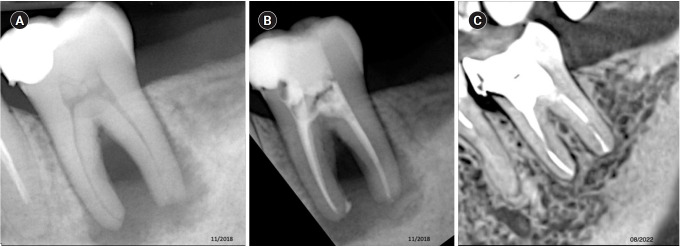

Methods: Teeth with apical lesions underwent endodontic treatment in which a high-power 810-nm diode laser with saline solution was used as monotherapy for disinfection. This type of therapy aimed to replace the traditional irrigation protocol with sodium hypochlorite. This research is the first to assess the clinical success of this alternative treatment, along with tomographic evaluations conducted over periods ranging from 2 to 7 years, analyzed using the periapical index based on cone-beam computed tomography (CBCTPAI). All cases were performed by a single clinician following the same laser protocol, which involved using 1 W of continuous power and four cycles of 20 seconds of laser activation.

Results: All teeth showed no clinical symptoms upon follow-up examination. However, the tomographic evaluation revealed that the success rates for teeth receiving primary treatment were 60% and 80% according to strict and loose criteria, respectively. For teeth requiring retreatment, the success rates were 12.5% and 37.5% using strict and loose criteria, respectively.

Conclusions: The teeth with apical lesions that underwent primary treatment did not present clinical symptoms, but they showed a moderate success rate on tomographic evaluation. However, despite lacking clinical symptoms, teeth with apical lesions that required retreatment had a very low success rate on tomographic evaluation.